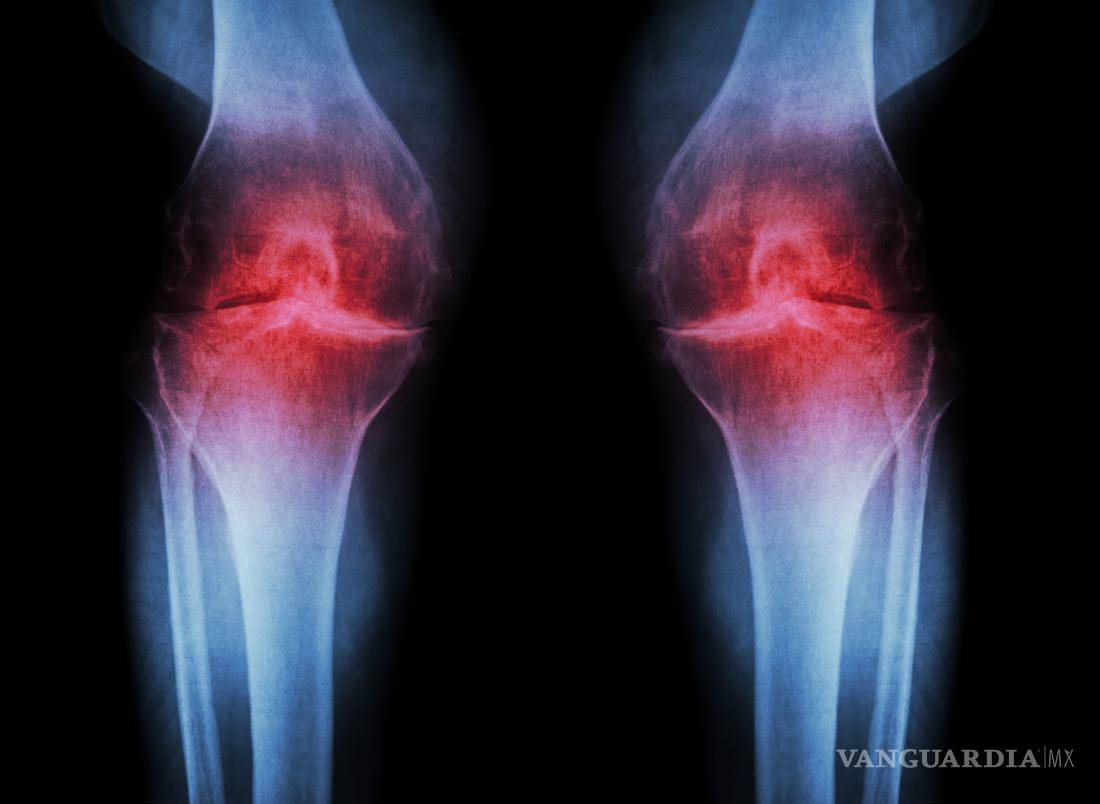

El sobrepeso genera mayor desgaste en las articulaciones

La osteoartritis es un padecimiento crónico-degenerativo que ocasiona destrucción gradual y progresiva del cartílago que cubre las rodillas, cadera, hombros, manos, tobillos y columna vertebral. A escala global, alrededor de 15 por ciento de la población mayor de 60 años de edad la padece y ahora cada vez más adultos jóvenes y de mediana edad desarrollan el padecimiento. Está comprobado que adultos entre los 22 y 55 años que experimentan este mal en cadera o rodillas son cuatro veces más propensos a sufrir altos niveles de estrés y depresión, además de que 67 por ciento reporta invalidez labo-ral, sostuvo.

La osteoartritis es considerada la más común de las enfermedades reumáticas crónicas. Entre estos padecimientos es de 10 a 12 veces más frecuente que la artritis reumatoide, con prevalencia en rodillas.